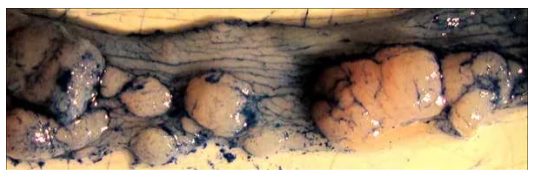

2. AOM/DSS造模50天后,與正常結(jié)腸(a)相比,模型組產(chǎn)生了多發(fā)性息肉樣腫塊阻塞末端結(jié)腸管腔(b、c)。

3. 處死后取小鼠結(jié)腸,可觀察形成的腫瘤。值得注意的是,末端結(jié)腸/直腸腫瘤負荷較高(左上圖),近端結(jié)腸腫瘤呈現(xiàn)褶皺狀紋理(右上圖),腫

瘤負荷很少。近距離觀察末端結(jié)腸可觀察到許多不同大小的腫瘤(下圖)。